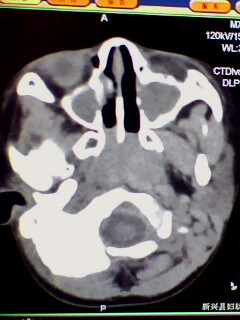

1)鼻咽腺样体肥大。2)双侧上颌窦、双侧筛窦及双侧蝶窦炎症。

鼻咽增殖体肥大、双侧上颌窦炎。

鼻咽腺样体肥大,副鼻窦炎。

腺样体肥大,鼻窦炎。